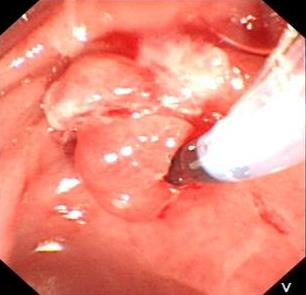

摘要:目的 探讨内镜下电凝切除术与冷切除技术治疗老年复杂性结肠息肉的临床疗效。方法 回顾性分析2021年8月-2023年8月于该院消化内科行内镜下结肠息肉电凝切除和冷切除治疗的100例老年结肠息肉患者的临床资料。根据手术方式的不同,将患者分为电凝组(50例)和冷切组(50例)。统计两组老年结肠息肉患者的息肉切除情况、术中及术后治疗情况、术后疼痛程度、胃肠道生活质量指数(GIQLI)评分、住院时间、治疗总费用,以及随访1年后的复发情况。结果 电凝组共切除息肉108枚,冷切组共切除息肉113枚,冷切组息肉完整切除率高于电凝组,标本受损率低于电凝组,差异均有统计学意义(P < 0.05);两组患者平均息肉切除数量和标本回收率比较,差异均无统计学意义(P > 0.05)。冷切组手术时间和住院时间短于电凝组,治疗总费用少于电凝组,术中钛夹使用率低于电凝组,差异均有统计学意义(P < 0.05)。电凝组术中出血、迟发出血、穿孔和腹痛发生率分别为6.00%、2.00%、2.00%和6.00%,高于冷切组的2.00%、0.00%、0.00%和2.00%,两组患者并发症总发生率比较,差异有统计学意义(P < 0.05)。冷切组术后24和48 h的视觉模拟评分法(VAS)评分低于电凝组,差异均有统计学意义(P < 0.05)。冷切组术后3个月的GIQLI评分高于电凝组,差异有统计学意义(P < 0.05)。冷切组术后1年的复发率低于电凝组,但两组患者比较,差异无统计学意义(P > 0.05)。结论 内镜下冷切除技术治疗老年复杂性结肠息肉患者,临床疗效较电凝切除术好,且安全性高,治疗费用少。值得临床推广应用。